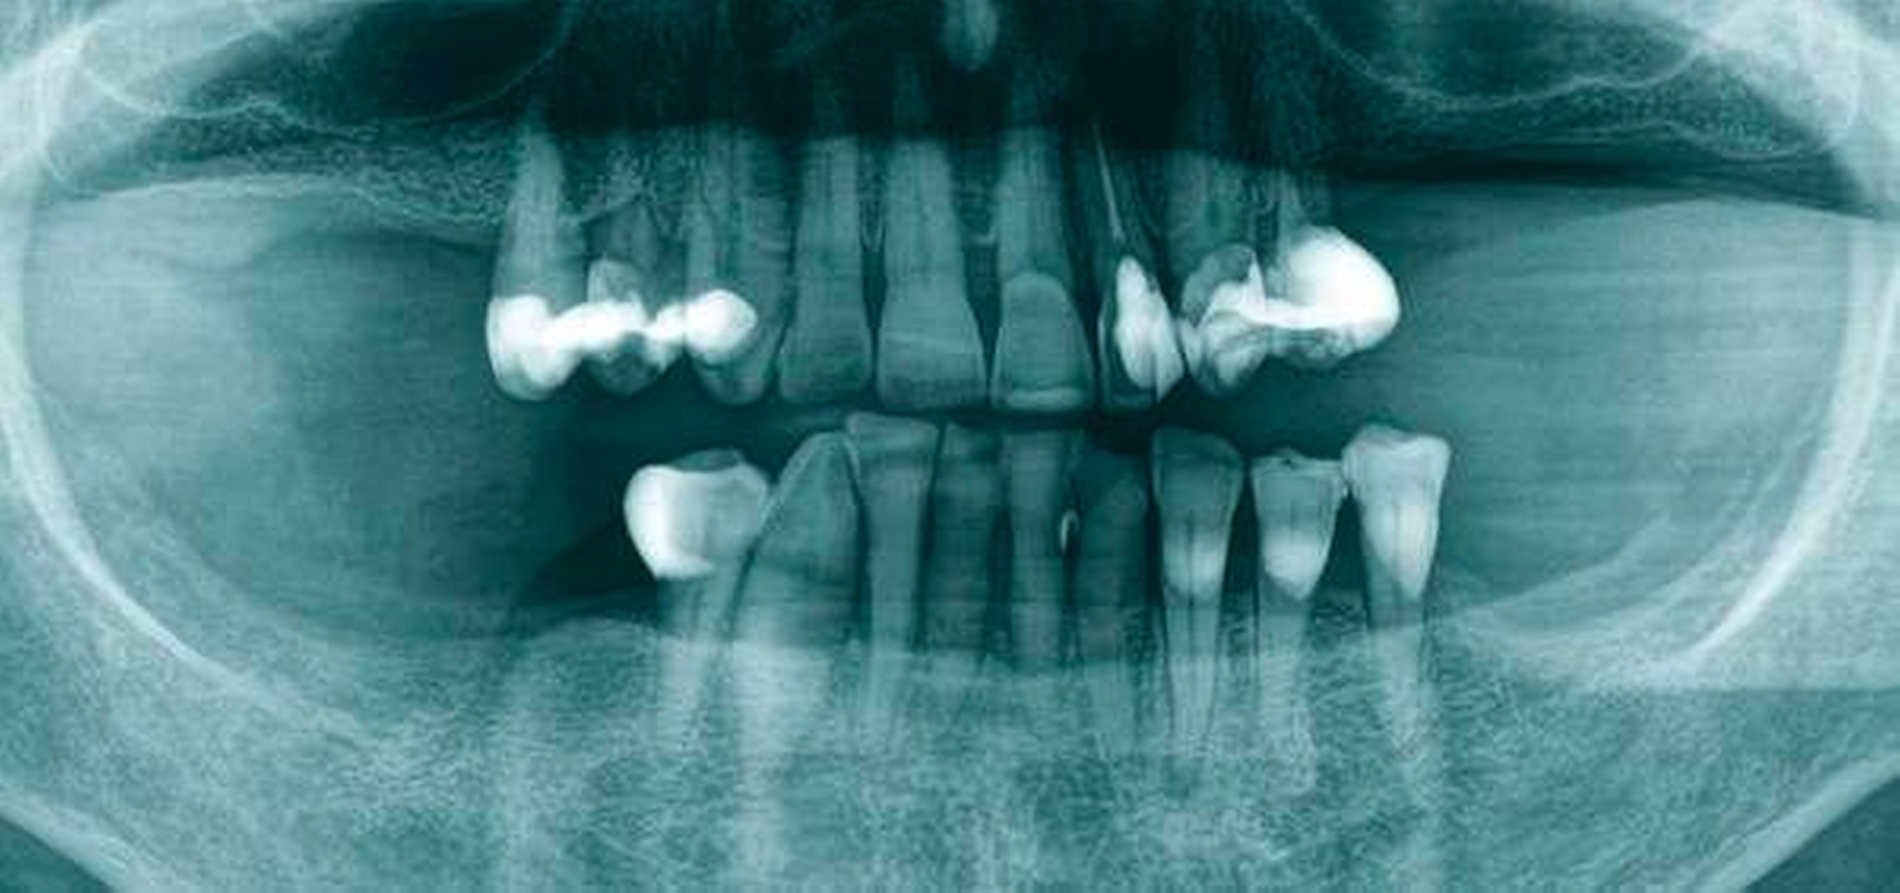

Abbildung 1a bis 1f: Direkte Überkronung im Frontzahnbereich (R1-Technik)

In den Abbildungen 1 bis 3 werden Optionen für frugale Interventionen auf restaurativem Sektor aufgeführt. Es handelt sich um direkte Vollüberkronungen im Frontzahnbereich (hier: hergestellt in R1-Technik / einphasig) (Abbildung 1), direkte Teilüberkronungen im Seitenzahnbereich (hier: hergestellt in R1-Technik / einphasig) (Abbildung 2), Reparatur-Restaurationen im Seitenzahnbereich (hier: hergestellt in R2-Technik / zweiphasig) (Abbildung 3). Technische Einzelheiten zur Vorgehensweise und den Ergebnissen sind an anderer Stelle beschrieben (Literatur siehe oben).

Am Beispiel von Abbildung 1 (stark zerstörte Zahnkrone eines Schneidezahns) kann das Prinzip der frugalen Intervention erläutert werden:

Früher wurde für die hier beschriebene Ausgangssituation folgendes Procedere gewählt:

Wurzelkanalbehandlung des vitalen Zahns als Voraussetzung für eine Stiftversorgung

Einsetzen eines Wurzelkanalstifts

Einsetzen einer indirekt gefertigten Stiftkrone

Durch die Erfolge der Adhäsiv- und Komposittechnik kann heute folgendermaßen vorgegangen werden:

Verzicht auf Wurzelkanalbehandlung / Erhaltung der Vitalität des Zahns

Verzicht auf Wurzelkanalstift

direkte minimalinvasive Kompositkrone (Verzicht auf indirekte Vorgehensweise)

Die potenziellen medizinischen und ökonomischen Vorteile dieser frugalen Intervention sind vielfältig:

Schonend: Die oralen Strukturen werden geschont und die Versorgung ist hinreichend stabil. Durch den Verzicht auf Wurzelkanalstifte wird das Wurzelfrakturrisiko reduziert. Zudem können Material-, Geräte- und Personalressourcen aus Praxis und Techniklabor, die beim klassischen Vorgehen anfielen, reduziert werden.

Bezahlbar: Hier ist anzumerken, dass die Kosten unter anderem von der zahnärztlichen Expertise abhängig sind: Zahnärzte, die mit direkten Restaurationen große Erfahrung haben, können zügiger und mit besserem Erfolg arbeiten als Kollegen mit geringerer Erfahrung auf diesem Gebiet; die Behandlung ist gleichwohl anspruchsvoll und deshalb nicht „billig“. Eine direkte Vorgehensweise kann, muss aber nicht automatisch zeit- und kostensparender sein als eine Versorgung mit indirekt hergestellten Werkstücken.

Gut genug: Ästhetische Feinheiten lassen sich bei direkten Restaurationen nicht immer in gleicher Perfektion einarbeiten wie bei indirekt gefertigten Kronen, auch die Stabilität des Hochglanzes lässt bei einigen Kompositpräparaten noch zu wünschen übrig. Andererseits erlauben die direkten Verfahren inzwischen mitunter sehr flexible Vorgehensweisen, die sich auch mit Farb- und Formkorrekturen von Zähnen kombinieren lassen. Die Erwartungen eines großen Teils der Patienten werden hinreichend erfüllt und die Nutzen-Risiko-Relationen wie auch die Aufwand-Kosten-Relationen erscheinen – wenn auch nicht durchgängig – so doch zumindest in vielen Fällen günstig.